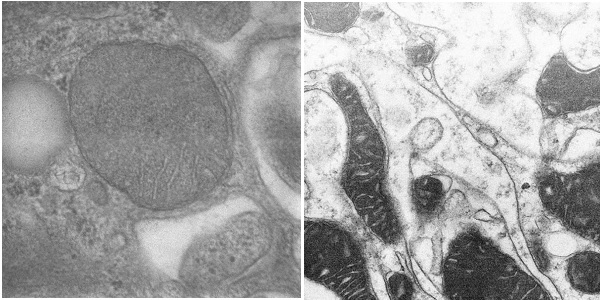

图4. 利用SmartView对病理组织切片样品进行成像(高倍STEM像)

项目从医院病理科电镜病理检测存在的仪器维护成本高、操作复杂、通量低、人力成本高等痛点出发,成功研制了针对病理组织切片样品的高通量扫描透射电子显微镜SmartView(图1),发明了载网托盘和新型的装载方式(图2),一次可以装载500个病理切片载网,实现了8K*8K的高速扫描透射成像能力,仪器成像分辨率优于1.1nm,可以进行病理组织切片样品高速和高质量成像(图3,图4),将有效推动生物医学病理电镜检测快速发展。

上午,项目负责人孙飞研究员向评审技术专家组介绍了项目背景和项目技术指标验收方案并得到专家组认可。随后,项目研发总监曹峰高级工程师带领评审技术专家组根据验收方案对研制的高通量扫描透射电子显微镜的各项技术指标(分辨率、加速电压稳定性、电子束流及其稳定性、高通量样品台和成像质量等)进行了现场考察和测试(图5)。通过各位专家对几种不同类型电镜照片盲测评分的数据统计,SmartView拍摄照片质量与120kV透射电镜所拍摄照片在生物切片样本成像质量方面相当,满足病理组织切片样品电镜检测的要求。